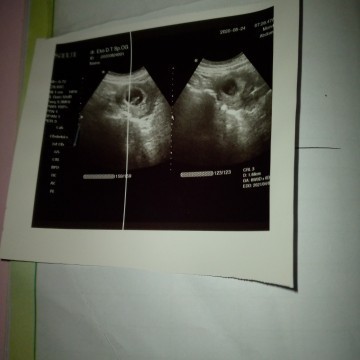

Apakah foto itu benar sesuai umur kandungan ku 8 minggu

Saya tidak mengerti tentang gambar usg ingin tolong jelas kan

nah di baca aja di bawha tuh GA tulisannya berapa, kalo 8w bener